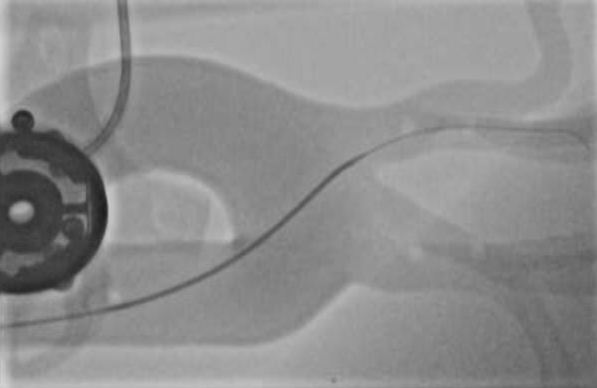

Qualitative Results. Fig. 5 illustrates the catheter and guidewire segmentation results of fine-tuning ViT on our method and different foundation models. The visualization portrays that our method excels in accurately delineating the catheter and guidewire structures, showcasing superior segmentation performance compared to other approaches. This figure further confirms that we can successfully train a federated endovascular foundation model without collecting users’ data and the trained foundation model is useful for the downstream segmentation task.

|

Animal |

Phantom |

Simulation |

Input

Ground Truth

LVM-Med

SAM

CLIP

Ours